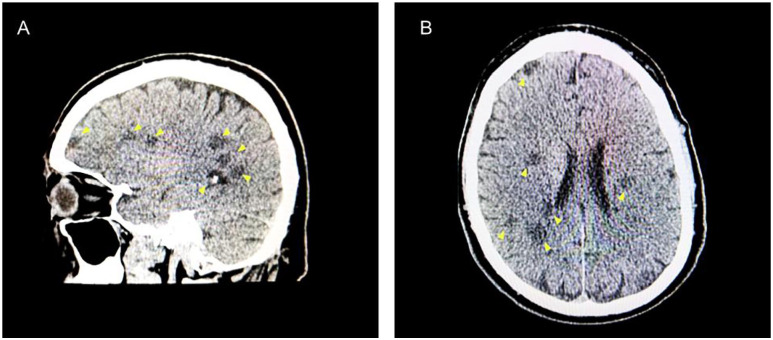

Nontraumatic clostridial myonecrosis infections are predominantly caused by Clostridium septicum. Most patients have an underlying gastrointestinal malignancy. This case presents a rare association of spontaneous clostridial myonecrosis preceding cerebral septic emboli with underlying invasive colorectal adenocarcinoma. A 60-year-old male with a history of hypertension, diabetes, and a family history of colon cancer presented to the emergency room with worsening left-sided chest pain radiating to his left shoulder. Extensive workup revealed elevated D-dimer, troponin, C-reactive protein, white blood cell count, and creatinine phosphokinase. Due to his clinical signs, symptoms, elevated white count, and further decompensation, he was started on antibiotics for sepsis. Physical exam revealed left upper extremity (LUE) crepitus consistent with imaging of innumerable soft tissue gas collections along the LUE. Incision, drainage, and myomectomy were performed due to concerns of myositis and necrotizing infection. Muscle biopsy revealed myonecrosis, and subsequent samples were positive for C. septicum. Postoperative pressor support and several sessions of surgical debridement were required. He continued to deteriorate and developed left-sided paralysis. Computed tomography head revealed several white matter infarcts indicative of septic emboli. The patient slowly recovered neurologically after switching to central nervous system-penetrating antibiotics. Months later, a colonoscopy revealed cecal adenocarcinoma. This case features a unique course of spontaneous C. septicum infection. There are high mortality rates, and previous studies report an association with colorectal malignancies. Therefore, preventative and diagnostic evaluations are imperative with a confirmed C. septicum infection. To our knowledge, this is the first case reported of cerebral septic emboli secondary to spontaneous myonecrosis with C. septicum, highlighting a unique burden of emboli-induced neurological deficits.